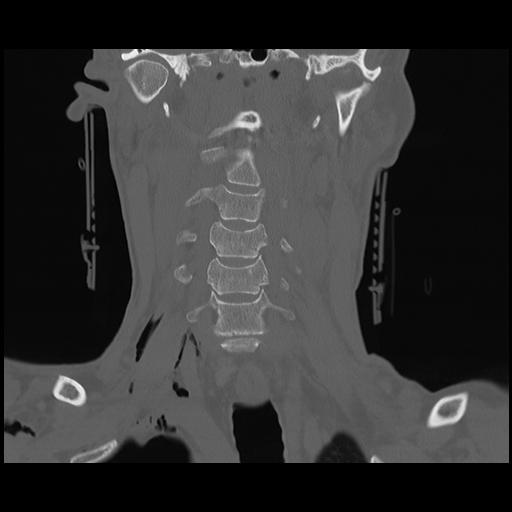

16 HUESO,,Coronal,2.000,HUESO,Coronal,